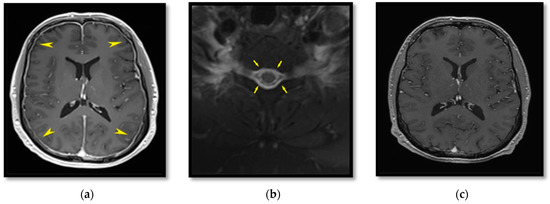

2.1. Patient I

2.2. Patient II

2.3. Patient III